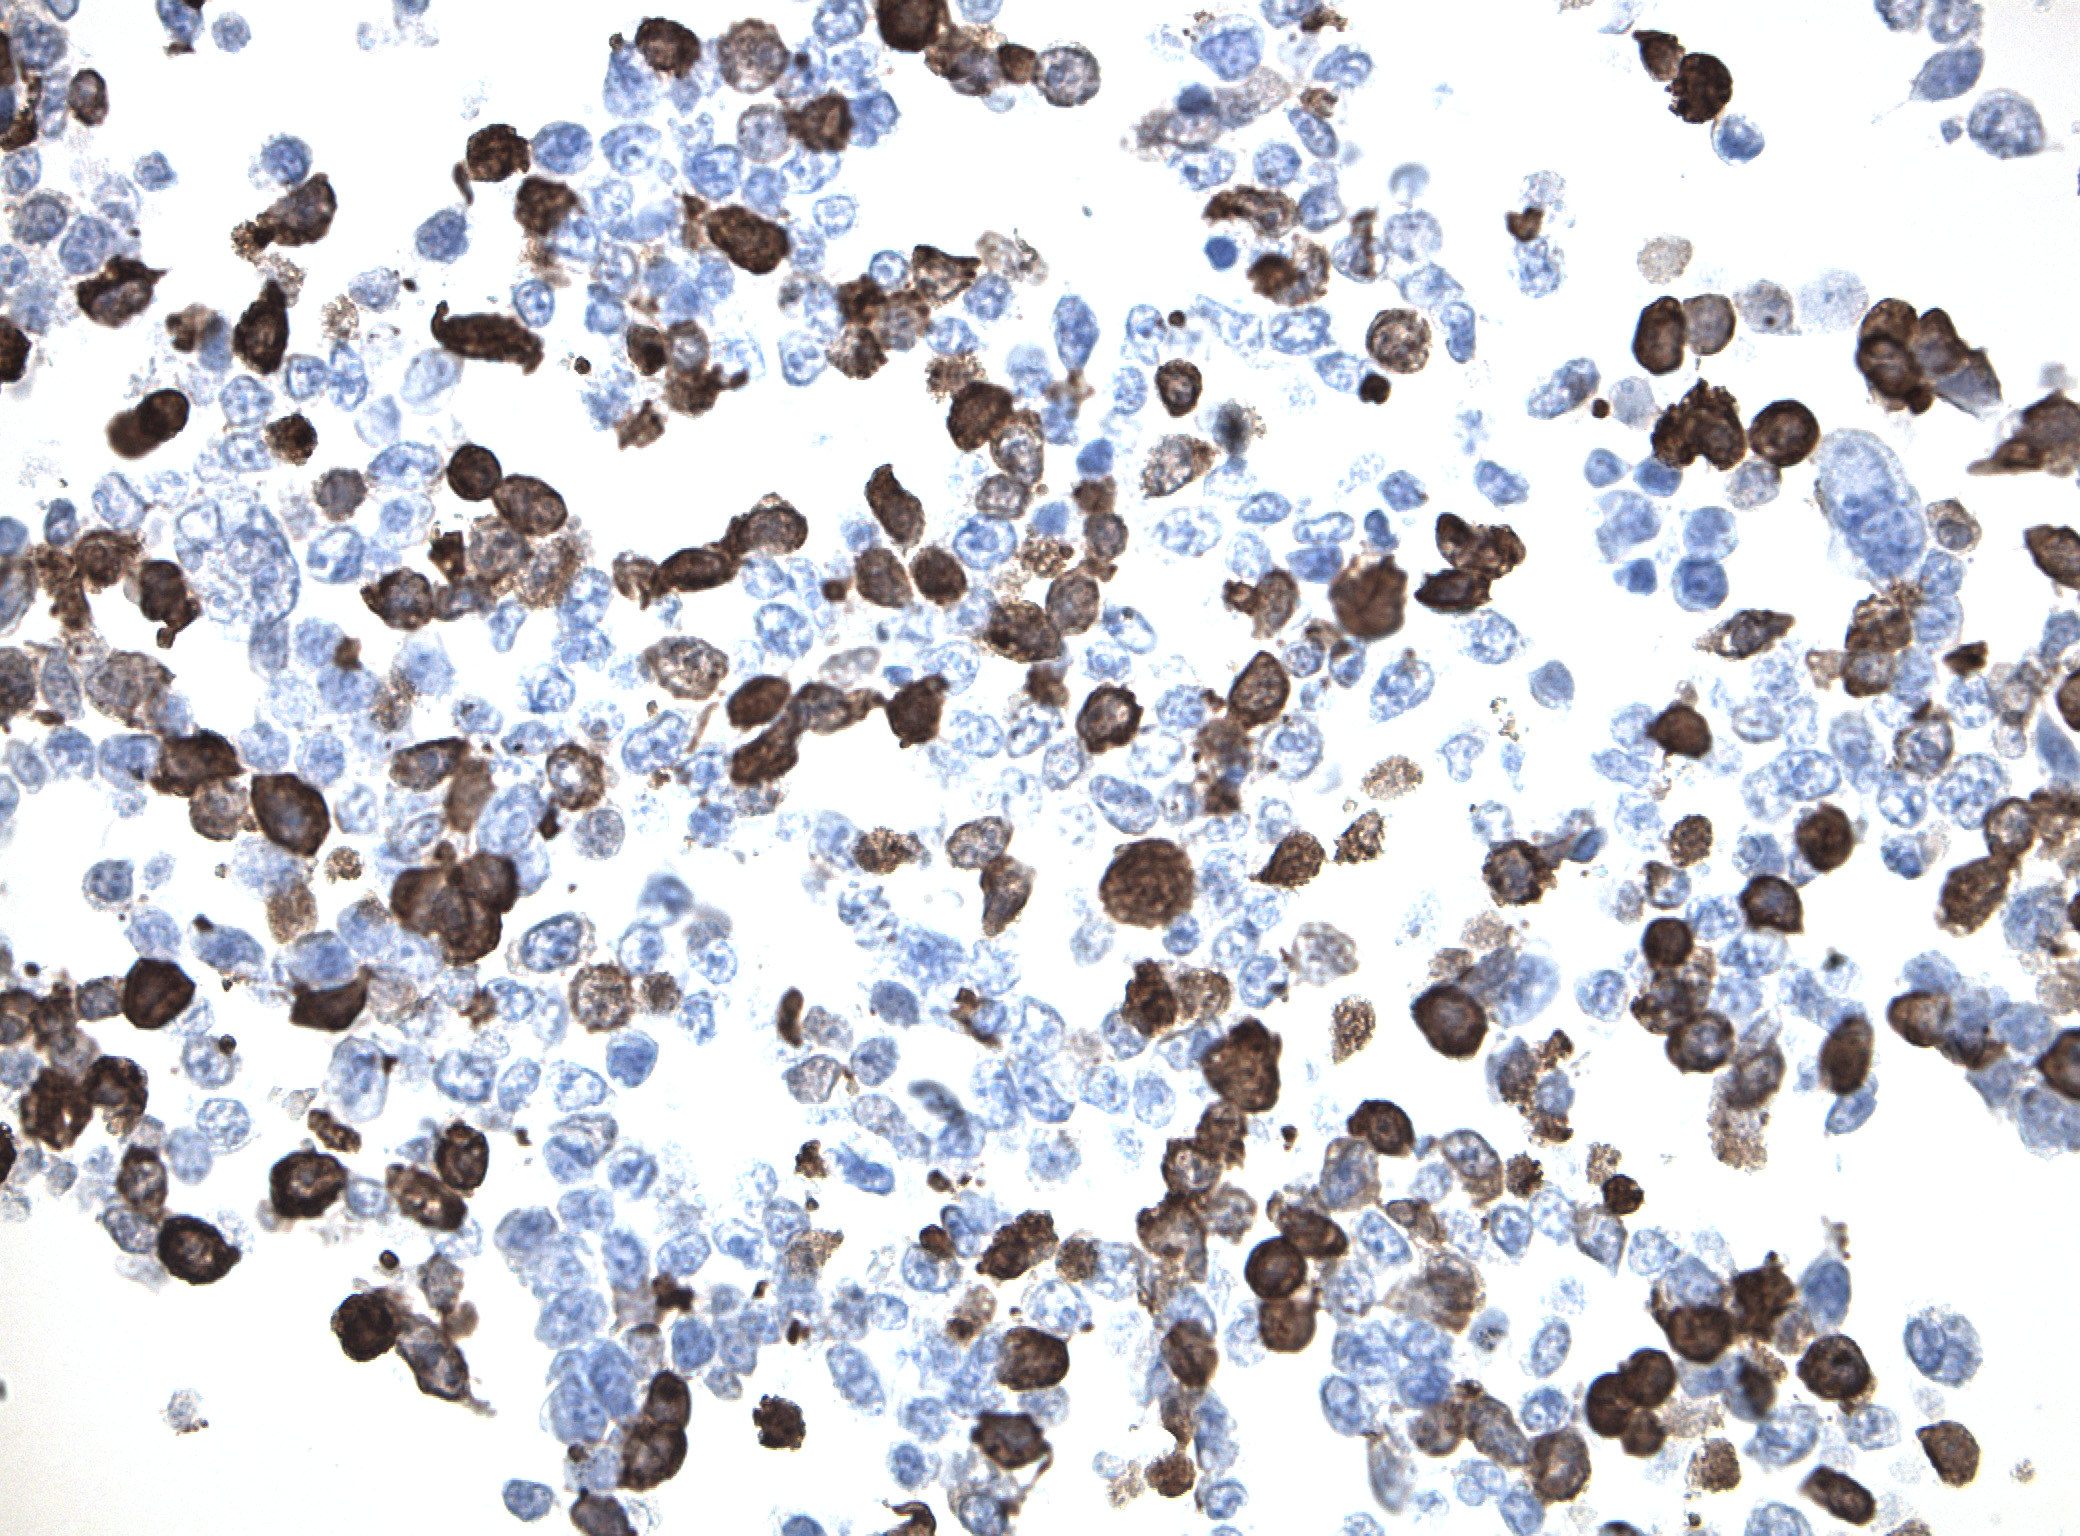

IDH1 (R132H) Mutant-Specific Antibody Screening, Validation, and Specificity

CytoSections enables identifying the right antibody for your research. See how CytoSections, featuring WT or mutant IDH1 (R132H) protein, helped screening and validation of specific antibody against the mutant IDH1 (R132H).

CytoSections |

IDH1 (WT) |

IDH1 (R132H) |

IDH1 (WT) |

IDH1 (R132H) |

|

IDH1 (R132H) Antibody |

Reactivity |

None |

Strong |

None |

Mild |